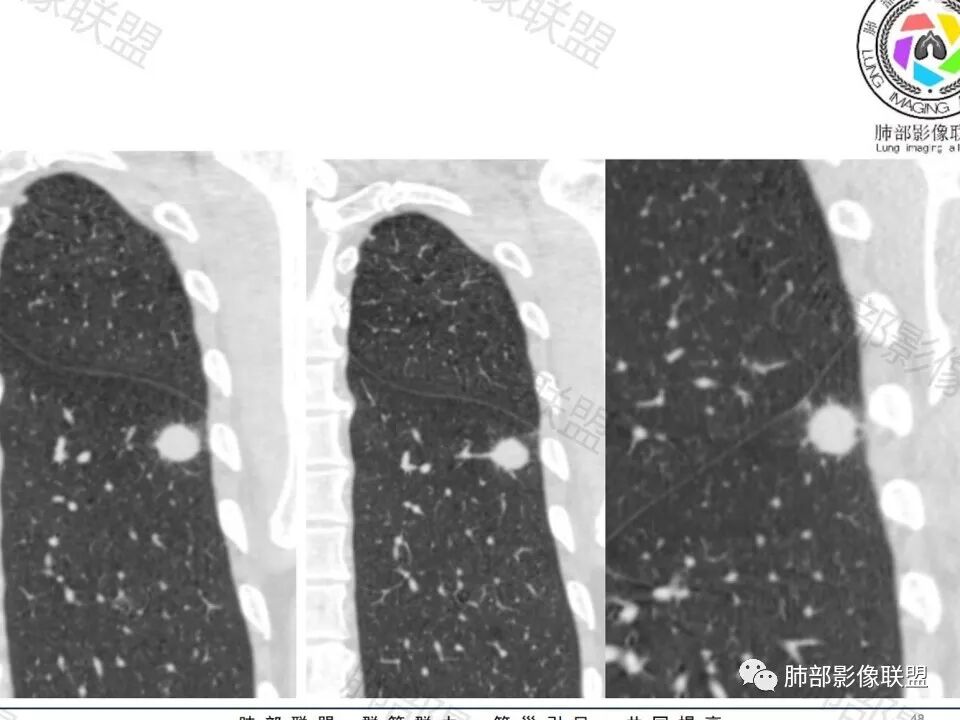

左下肺、右中肺均有结节,左下肺病灶比较鼓,边缘有晕,血管弯,持续性强化,考虑腺癌可能,鉴别两处病灶如果一元论,肉芽肿炎 (隐球)

图做的真漂亮!老年男性,双肺多发结节,最大者位于左肺下叶胸膜下,周围有晕,晕中毛刺,边缘有一囊腔,胸膜牵拉,持续强化,考虑隐球,鉴别腺癌。

左肺下叶胸膜下类圆形结节,边缘光滑,周围有晕,晕中有毛刺,周围可见小卫星灶,相邻胸膜增厚,血管进入,右肺中叶可见小结节影,考虑炎性肉芽肿,隐球菌。鉴别腺癌。

晨读:左肺下叶胸膜下实性小结节,边缘可见模糊晕及毛刺,轻度收缩,与支气管关系不清,近端与血管束相连,内见小空泡,平扫密度均匀,均匀强化。远近可见多个小结节。考虑炎性肉芽肿,隐球菌病,鉴别结核、腺癌。

类圆形,边缘稍平直,周围晕中细微毛刺,密度均匀,均匀强化,血管走形自然,稍牵拉扭曲,支气管在近端堵塞

多发类似结节